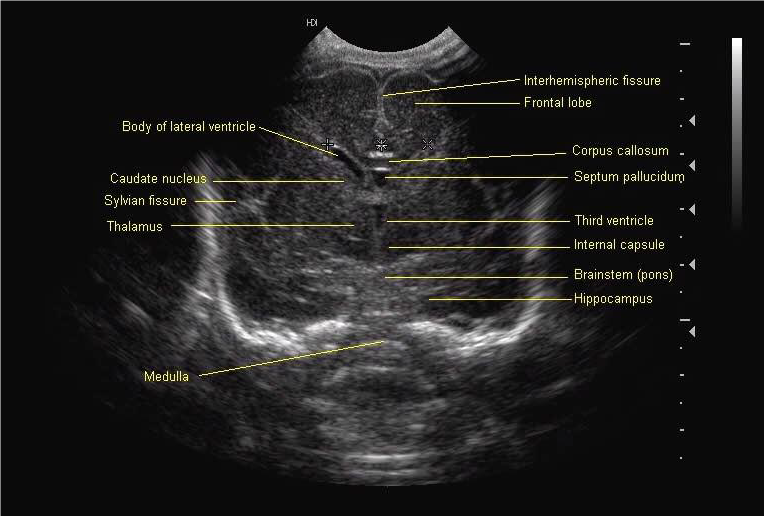

All scan results should be discussed with parents and, unless normal, this should be done by a member of the senior medical team. Although standard views for examination and hard copy print out are shown below, it is good practice to examine the peripheries of the brain including extreme lateral sagittal views, extreme anterior and posterior coronal views.

Mid Coronal